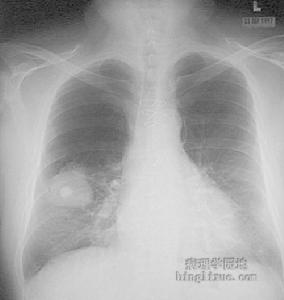

免疫缺陷性肺炎13.氧化代謝異常慢性肉芽腫病是吞噬細胞內氧化代謝異常的代表性疾病。吞噬細胞遭遇刺激如病原微生物入侵後不能提高氧耗,因而,不能產生超氧陰離子和過氧化氫,喪失氧化殺菌功能。常在10歲以內發病。皮膚、肺、骨骼和淋巴結最常受累。肺部感染表現包括瀰漫性浸潤、肺門淋巴結腫大或肺不張、肺膿腫形成、“局限性”肺炎等。病原體多為觸酶陽性菌如金黃色葡萄球菌和麴黴菌等,因為觸酶陽性菌破壞過氧化氫而使抗微生物防禦系統變得不完善。除針對病原體套用抗微生物藥物外,據報導Smzco對預防本病感染的發生有一定效果。感染灶的外科處理也是重要的。常規治療無效時可以輸注白細胞。感染是最常見死因,多數於兒童期夭亡,但也有生存至30歲以上者。氧化代謝異常的另一種疾病是萄萄糖-6-磷酸脫氫酶缺乏。臨床特點是溶血性貧血和反覆感染,主要為葡萄球菌和某些革蘭陰性桿菌感染。